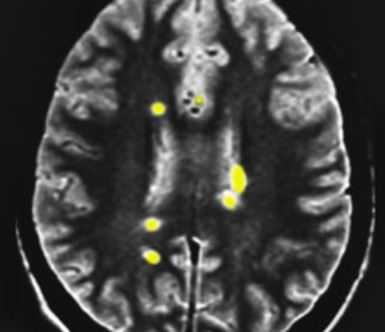

МРТ головного мозга. Т2-взвешенная аксиальная МРТ. Рассеянный склероз. Цветовая обработка изображения.

Демиелинизация - это разрушение оболочки аксона, отростка нервной клетки. Миелиновая оболочка играет роль «изоляции электропровода». При её нарушении нарушается проводимость электрического импульса.

Разными авторами предлагались критерии постановки диагноза. Все они основанный результатах МРТ головного мозга. Главным для постановки диагноза служит наличие нескольких (от 2 до 9) типично расположенных на МРТ очагов. Локализация очагов может быть любая, но типичная - нижняя треть мозолистого тела, перивентрикулярно (вокруг желудочков мозга), ствол, спинной мозг. Форма очагов округлая и овоидная, направленная радиально от желудочков на сагиттальных (боковых) МРТ (симптом “пальца” или Доусона), что отражает перивенулярный (вокруг вен) процесс. Существует много предложений по оценке активности процесса. К сожалению, все способы оценки активности очень недостоверны. Обычно края активных очагов нечёткие, отмечается слабое контрастирование. Чувствительность и специфичность МРТ на самых ранних стадиях составляет 70-80%. Однако через очень короткий срок течения заболевания точность МРТ уже приближается к 100%.

МРТ головного мозга. Рассеянный склероз. Аксиальная МРТ Т2-взвешенного типа. Перивентрикулярные очаги.